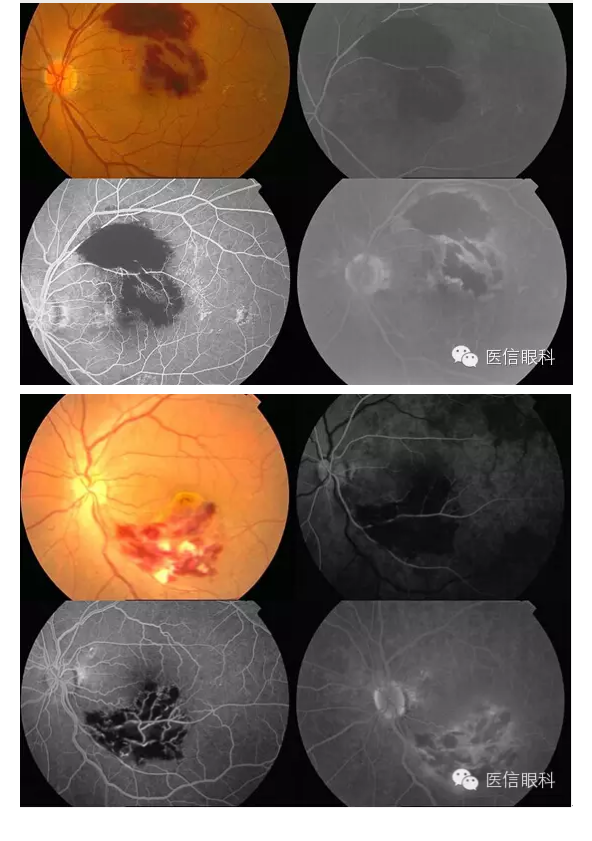

常见眼底病荧光血管造影表现(多图一)